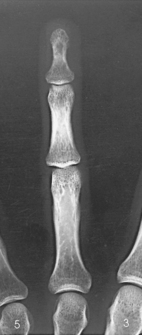

The digits contain 14 phalanges (phalanx, singular), which are long bones that consist of a cylindric body and articular ends. Nine phalanges have two articular ends. The first digit has two phalanges—the proximal and distal. The other digits have three phalanges—the proximal, middle, and distal. The proximal phalanges are the closest to the palm, and the distal phalanges are the farthest from the palm. The distal phalanges are small and flattened, with a roughened rim around their distal anterior end; this gives them a spatulalike appearance. Each phalanx has a head, body, and base.

Structures shown: A PA projection of the appropriate digit is visualized (Figs. 4-16 through 4-19).

Structures shown: A lateral projection of the affected digit is shown (Figs. 4-24 through 4-27).